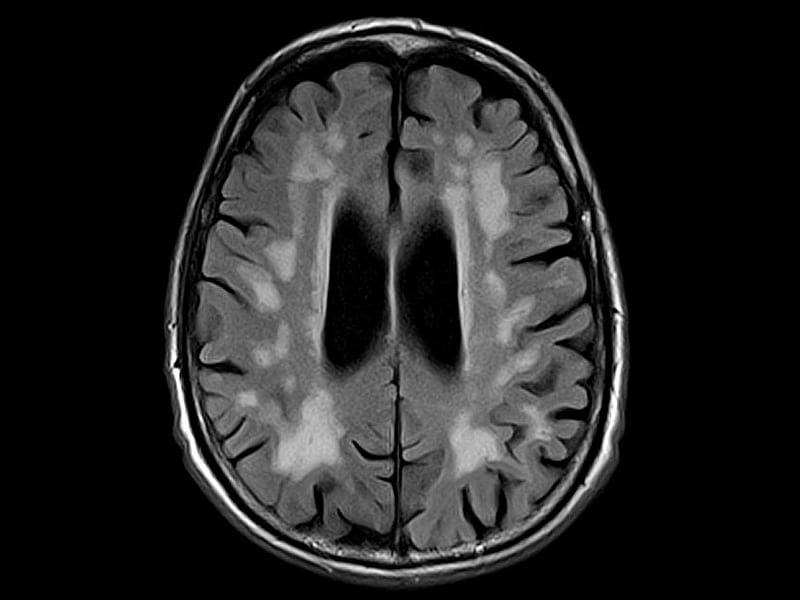

Хроническая ишемия головного мозга и лейкоареоз: симптомы и лечение